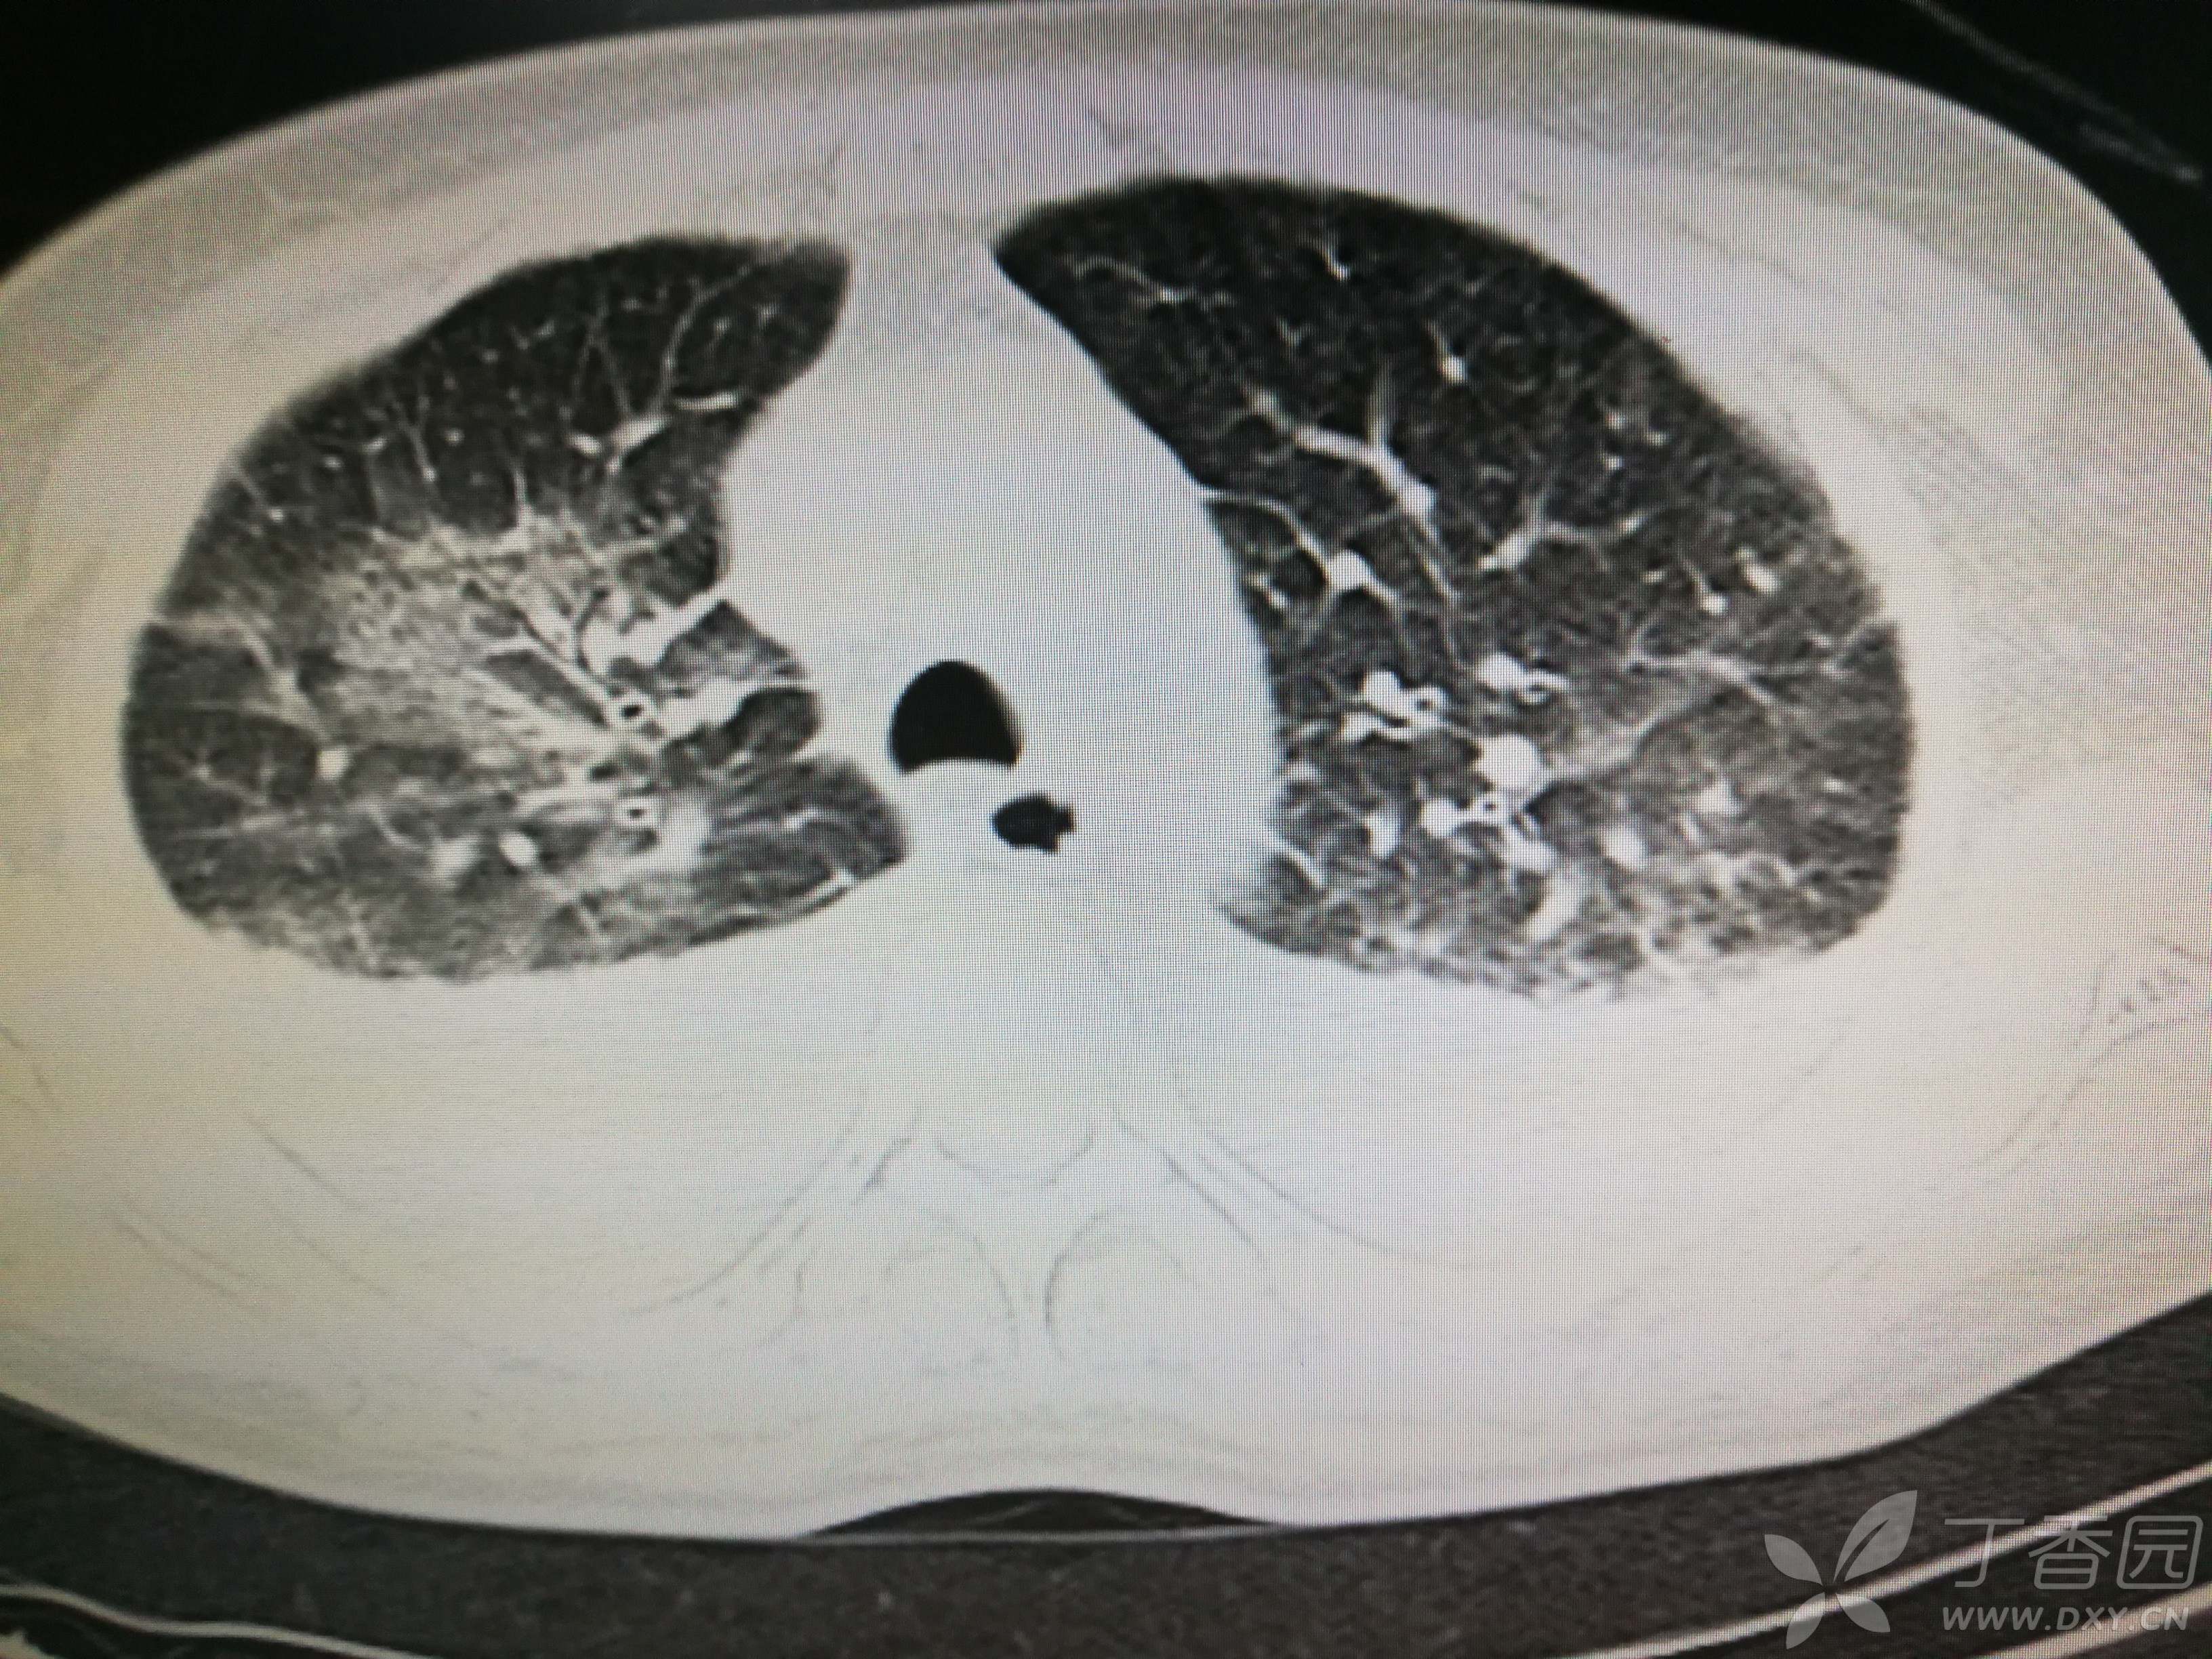

给予低分子肝素钙针抗凝、七叶皂苷钠针消肿及骨牵引固定等等治疗。入院后第四天行“左侧股骨下段骨折切开复位内固定术”(术前查双下肢彩超:双下肢深静脉血流通畅),手术顺利,术后予预防感染、预防血栓形成等治疗。术后患者无明显发热,生命体征平稳。术后第四天复查血常规:白细胞13.4×109/L,血红蛋白84g/L,血小板在正常范围。生化:白蛋白35.7g/L,余无明显异常。当天,患者开始出现轻度胸闷气急,可耐受。术后第五天患者胸闷气急加重,无胸痛,无背痛,无咯血,无意识障碍,无头晕头痛,无恶心呕吐等,急查凝血功能:纤维蛋白原降解产物12mg/L,D二聚体4000ug/L,余无明显异常。查动脉血气分析:pH7.52,氧分压62mmHg,二氧化碳分压30mmHg,碱剩余1.8mmol/L,乳酸1.0mm/L,血红蛋白86g/L。查胸部CT见下(先视频后图片):